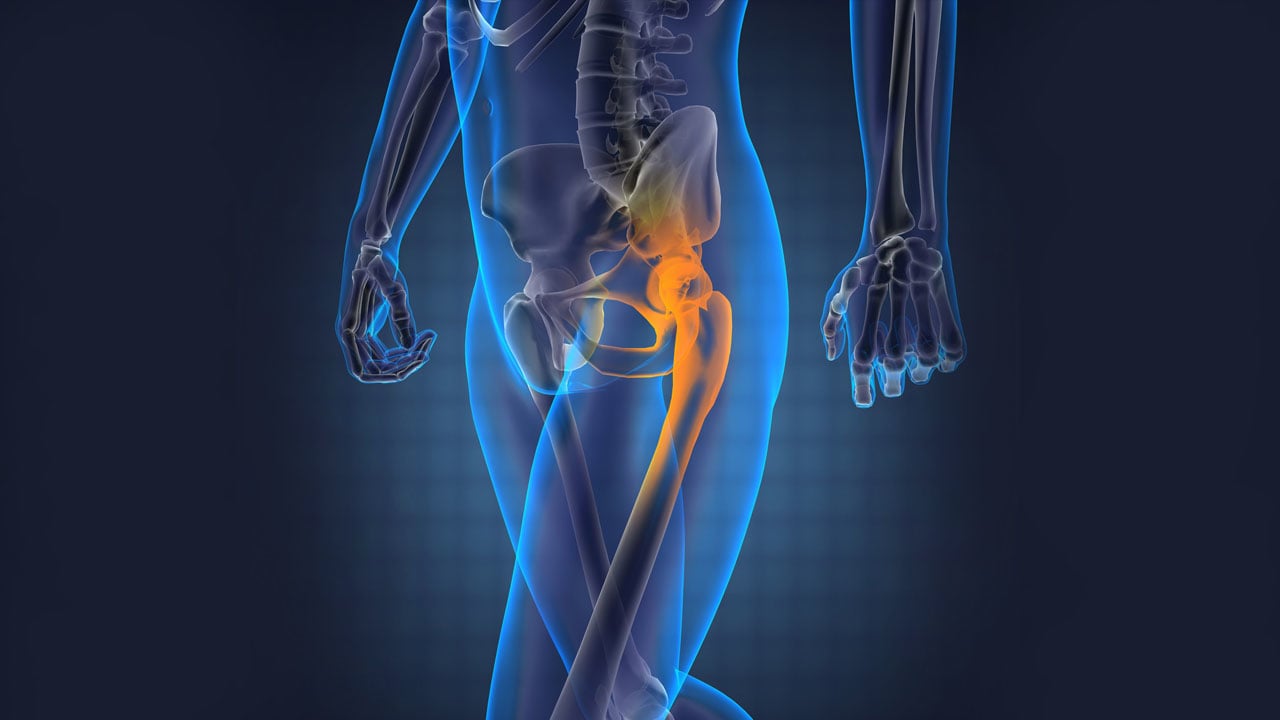

It is the process of restoring the hip joint to its normal position. Hip dislocation treatment usually requires emergency intervention and includes two main methods: closed reduction and surgical intervention. Closed reduction involves manually repositioning the hip joint. If this method fails or the dislocation is complicated, surgical intervention may be necessary. After treatment, physical therapy and rehabilitation are applied to restore joint functionality.

Hip dislocations that occur after an accident or trauma may require emergency treatment. In such cases, surgical intervention may be necessary quickly. In some situations, long-term hip dislocations can develop, and surgery is usually performed to stabilize the hip joint. Hip dislocation treatment may also involve hip replacement surgery if required.

In emergencies, the dislocated hip should be repositioned. This is done under anesthesia, either by manual manipulation or through surgical methods. Depending on the severity and condition of the dislocation, surgery may be required. This surgery is typically performed as a hip replacement or fracture repair. Hip replacement surgery is considered when the hip joint is severely damaged or has advanced arthritis. Postoperative rehabilitation is crucial. A physiotherapy program helps restore hip joint function and mobility.